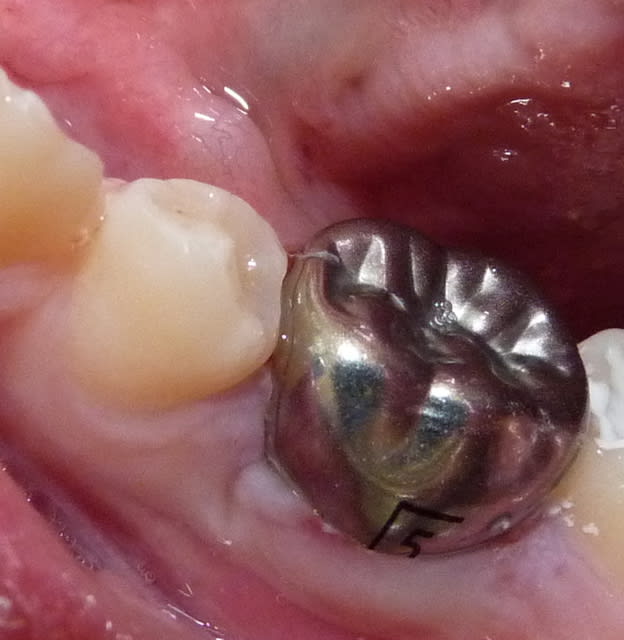

Qui ferait quoi dans le cas ci-dessous : 11 ans, patient en classe I, normodivergent, hygiène médiocre, très coopérant au fauteuil. 36 présente une carie similaire en lingual. Ces deux dents sont vitales.

P1010943 sukwth - Eugenol

Ext6 ka1zci - Eugenol

Gbazylo1 fvg1vg - Eugenol